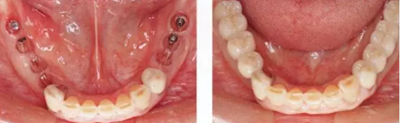

▲圖10-1,2

圖10-1 頰側和牙槽嵴有角化齦的存在,但是愈合期間內覆蓋螺絲露出(Type3-Class2)

▲圖10-3,4

圖10-3 第二次手術前的(牙合)面照。

圖10-4 為了在頰側、舌側進行FGG,在上頜腭側采集大塊移植片